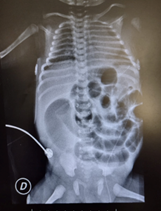

Ausencia de expulsión espontánea de meconio en las primeras 48 horas de vida, lo cual se acompaña de distensión abdominal y vómitos biliosos. Se deriva a una institución para valoración con cirujano pediátrico. Se realiza en ese momento radiografía de abdomen que muestra asas dilatadas simétricas y ausencia de gas a nivel distal. (Fig.1)